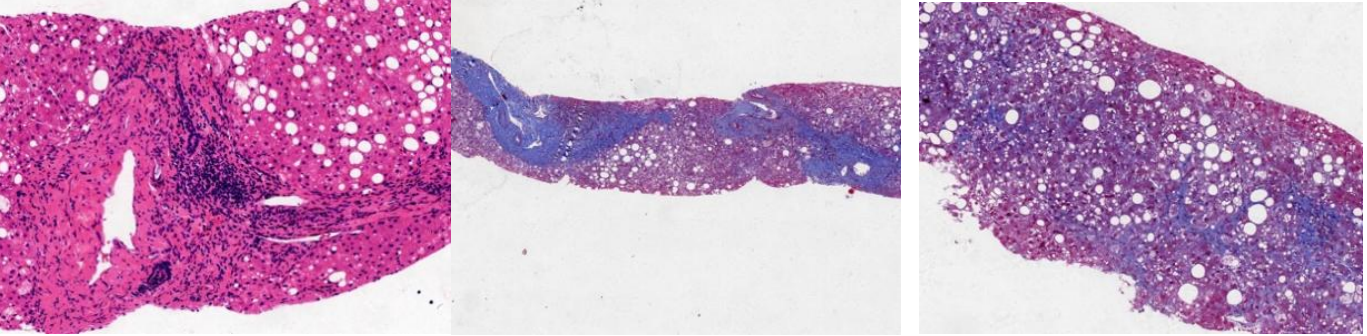

肝细胞脂肪变约40%(2分),气球样变明显(2分),小叶内可见点灶状坏死及桥接样坏死(2分),汇管区纤维组织增生,纤维隔形成,淋巴细胞,上皮样组织细胞浸润,少量浆细胞散在分布,局灶可见界板炎,小叶间胆管存在,汇管区周围小胆管轻度增生,未见淤胆。

免疫组化:HBsAg (-),CK7(+),CK19(+),Masson(++),网染(++),普鲁士蓝(散在阳性),PAS(+)

病理诊断:肝穿刺提示慢性活动性肝炎(G2S3),脂肪性肝炎(SAF:S2A4F3)。